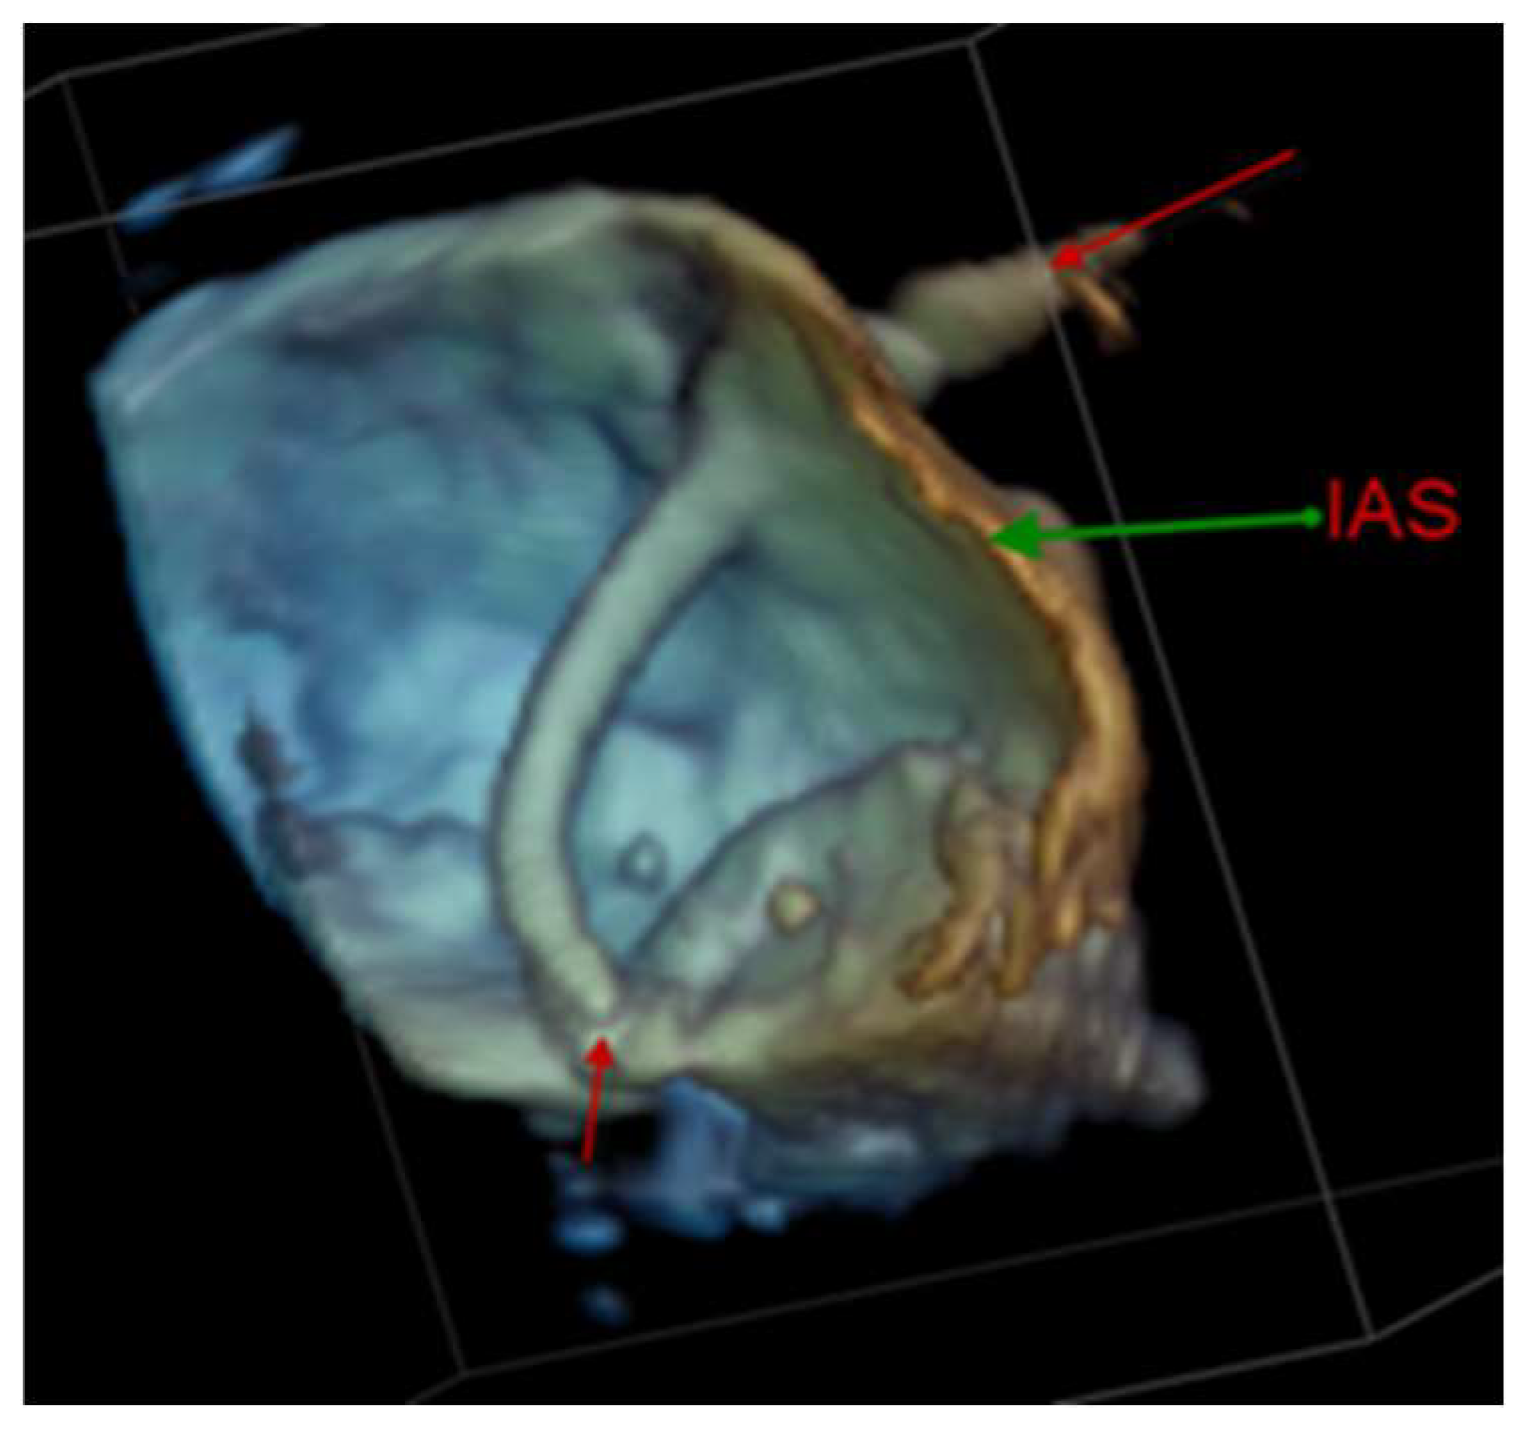

4.2.1. Transseptal Puncture

4.2.2. Left Atrial Appendage Occlusion